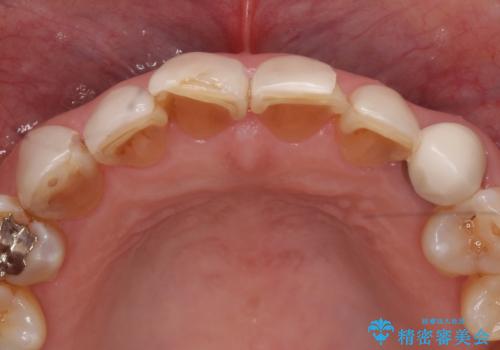

- 上下顎前歯部の見た目が気になるといらっしゃった方の症例です。

上顎は左4番から右4番までの8歯、下顎は左3番から右3番までの6歯、計14歯をオールセラミッククラウンにより補綴しました。

- 天然歯を削ります